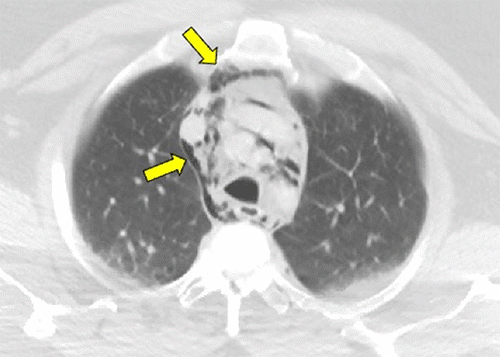

Figure 1. Noncontrast Computed Tomography of the Chest and Abdomen. Published with Permission

A) Chest CT depicting air in pneumomediastinum and B) abdomen CT depicting air in retroperitoneum—yellow arrows show air in both images.

A) Chest CT depicting air in pneumomediastinum—yellow arrows show air

On the secondary survey, he was found to have marked subcutaneous emphysema of the neck. The abdominal exam was benign, though the authors acknowledge that pain may not have been elicited on exam due to the patient's body habitus. There was an obvious deformity of the right lower extremity, confirmed by an X ray as a right subtrochanteric femur fracture. Noncontrast computed tomography images from the outside hospital demonstrated pneumomediastinum with subcutaneous emphysema, pneumoretroperitoneum, and moderate pneumoperitoneum with air infiltrating throughout the nondependent portions of the abdomen and mesentery.